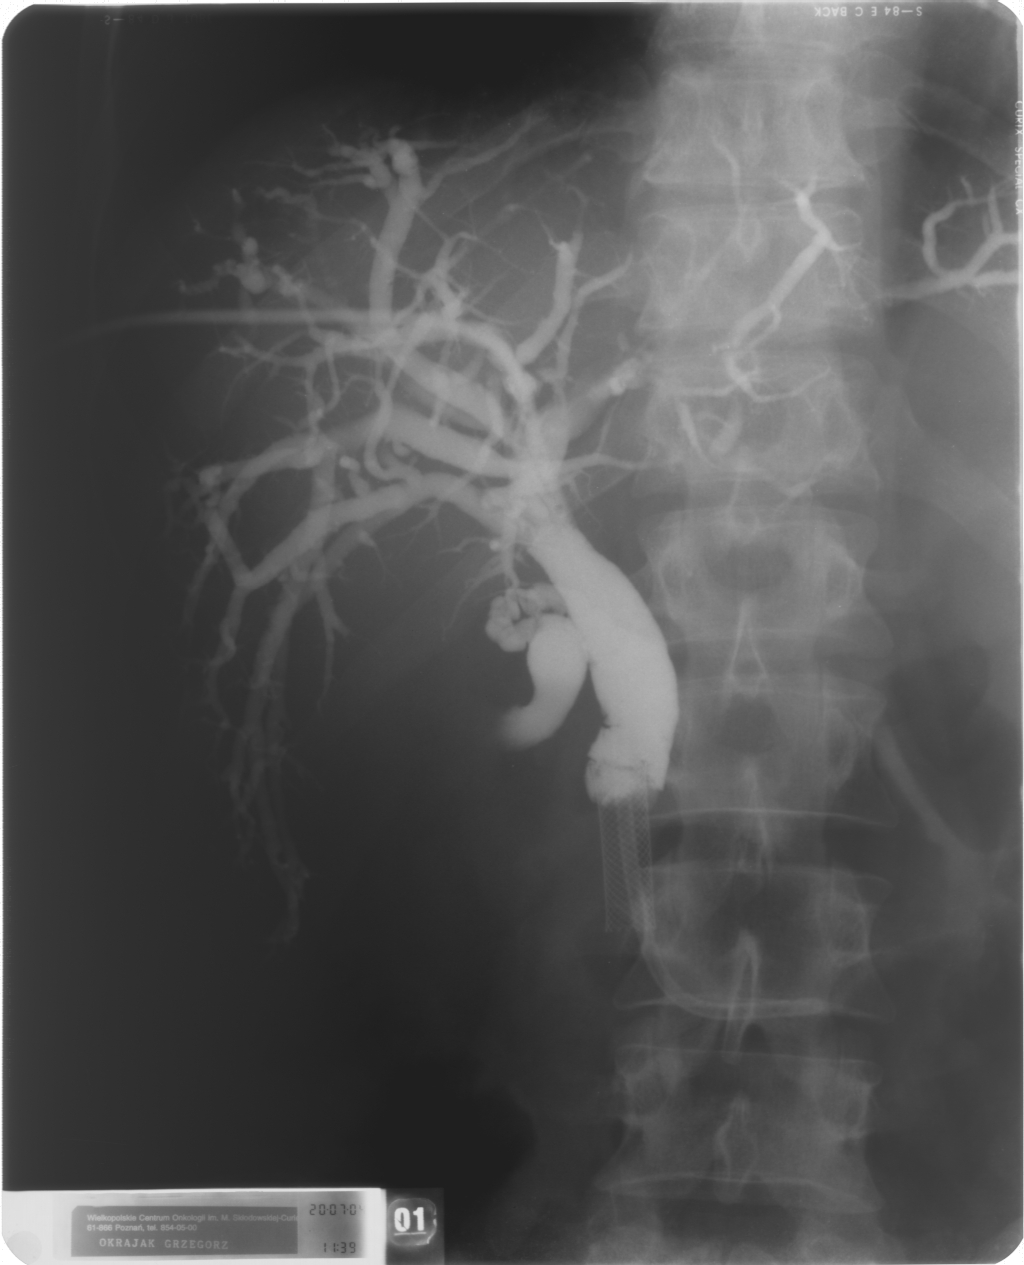

Cholangiografia - widok dróg żółciowych przed implantacją aplikatora do brachyterapii (French 5), założono dren 10 F metodą rendez-vous, widoczny stent